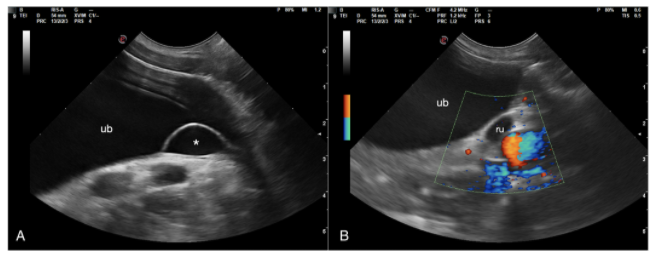

ureterocele에 의한 요도 폐색

본문 초반에 ureterocele이 uncommon 하다고 설명하고 있지만

특별한 이상증상이 없고 보호자가 수술적 교정을 원하지 않아 실제 임상증상이 유발된 경우는 보지 못하였으나

이번 논문에서처럼 크기가 증가하는 경우 폐색을 유발하여 이차적인 문제를 유발할 수도 있어서

조기에 수술적 교정을 해주거나 정기적인 모니터링을 해서 이상 변화를 확인해야 한다는 의미로 받아들여야 한다.